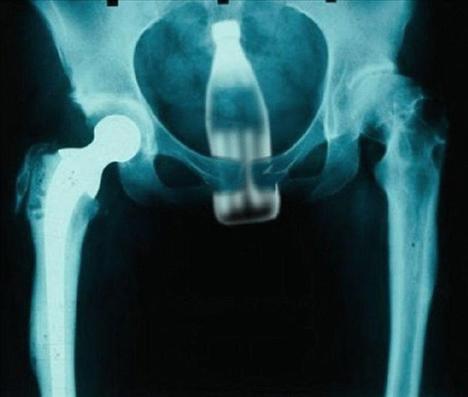

Şoke eden röntgen filmleri

Bu röntgen filmleri görenleri şaşkına çeviriyor!